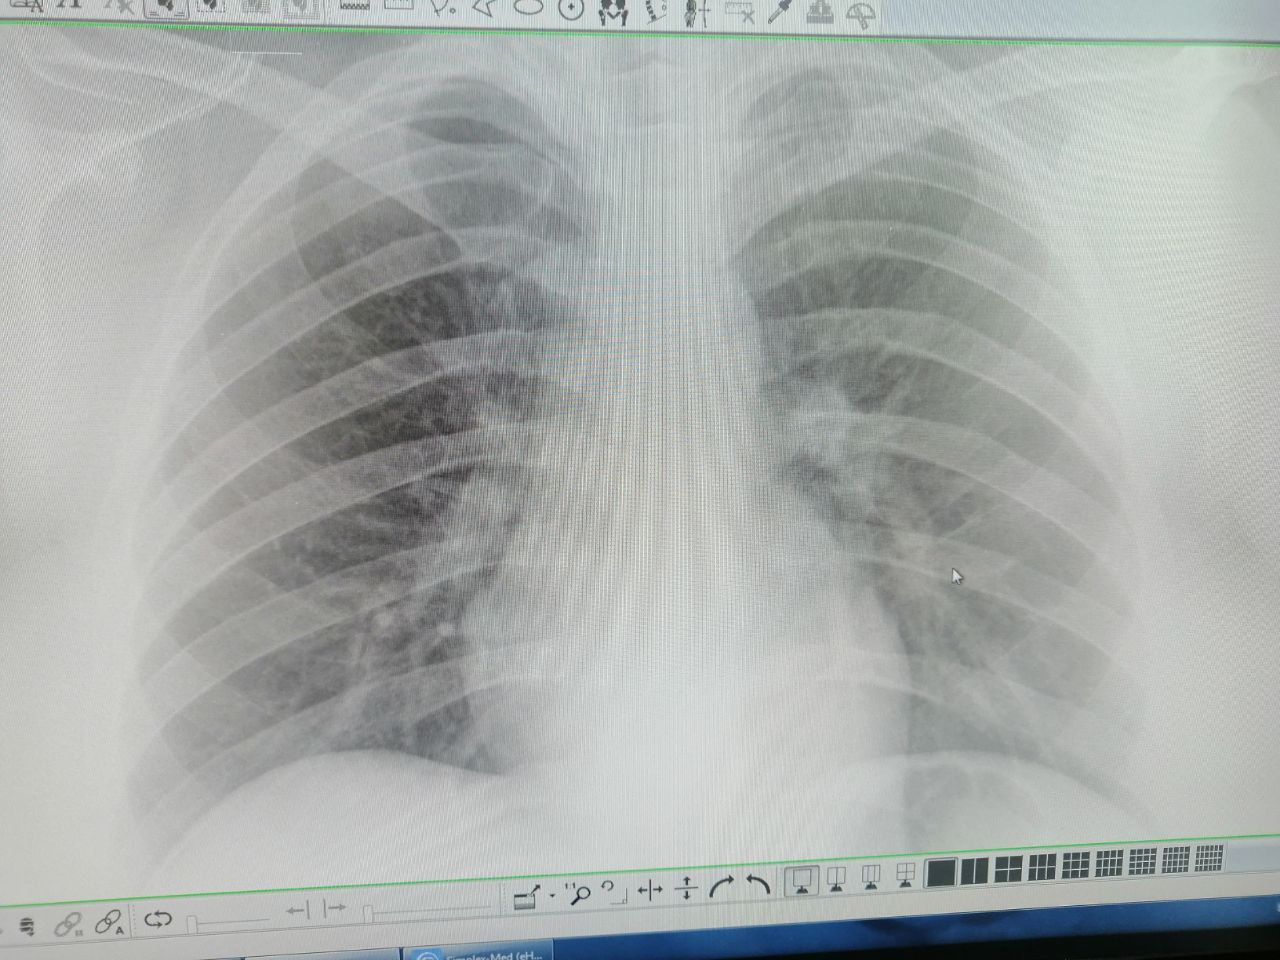

Подскажите пожалуйста что видите?

Центральный рак - из за того что отсутствует клиника кашля и температуры ?

Добрый день. Девушка 28л. Справа в 3 межреберье кальцинаты или сосуды?